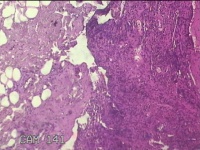

右侧耳垂结节

性别

男

年龄

24岁

临床诊断

耳垂新生物

一般病史

发现右侧耳垂结节3个月余。

标本名称

大体所见

灰白暗红色结节0.5x0.3x0.2cm一个,表面糜烂。

不具诊断价值。